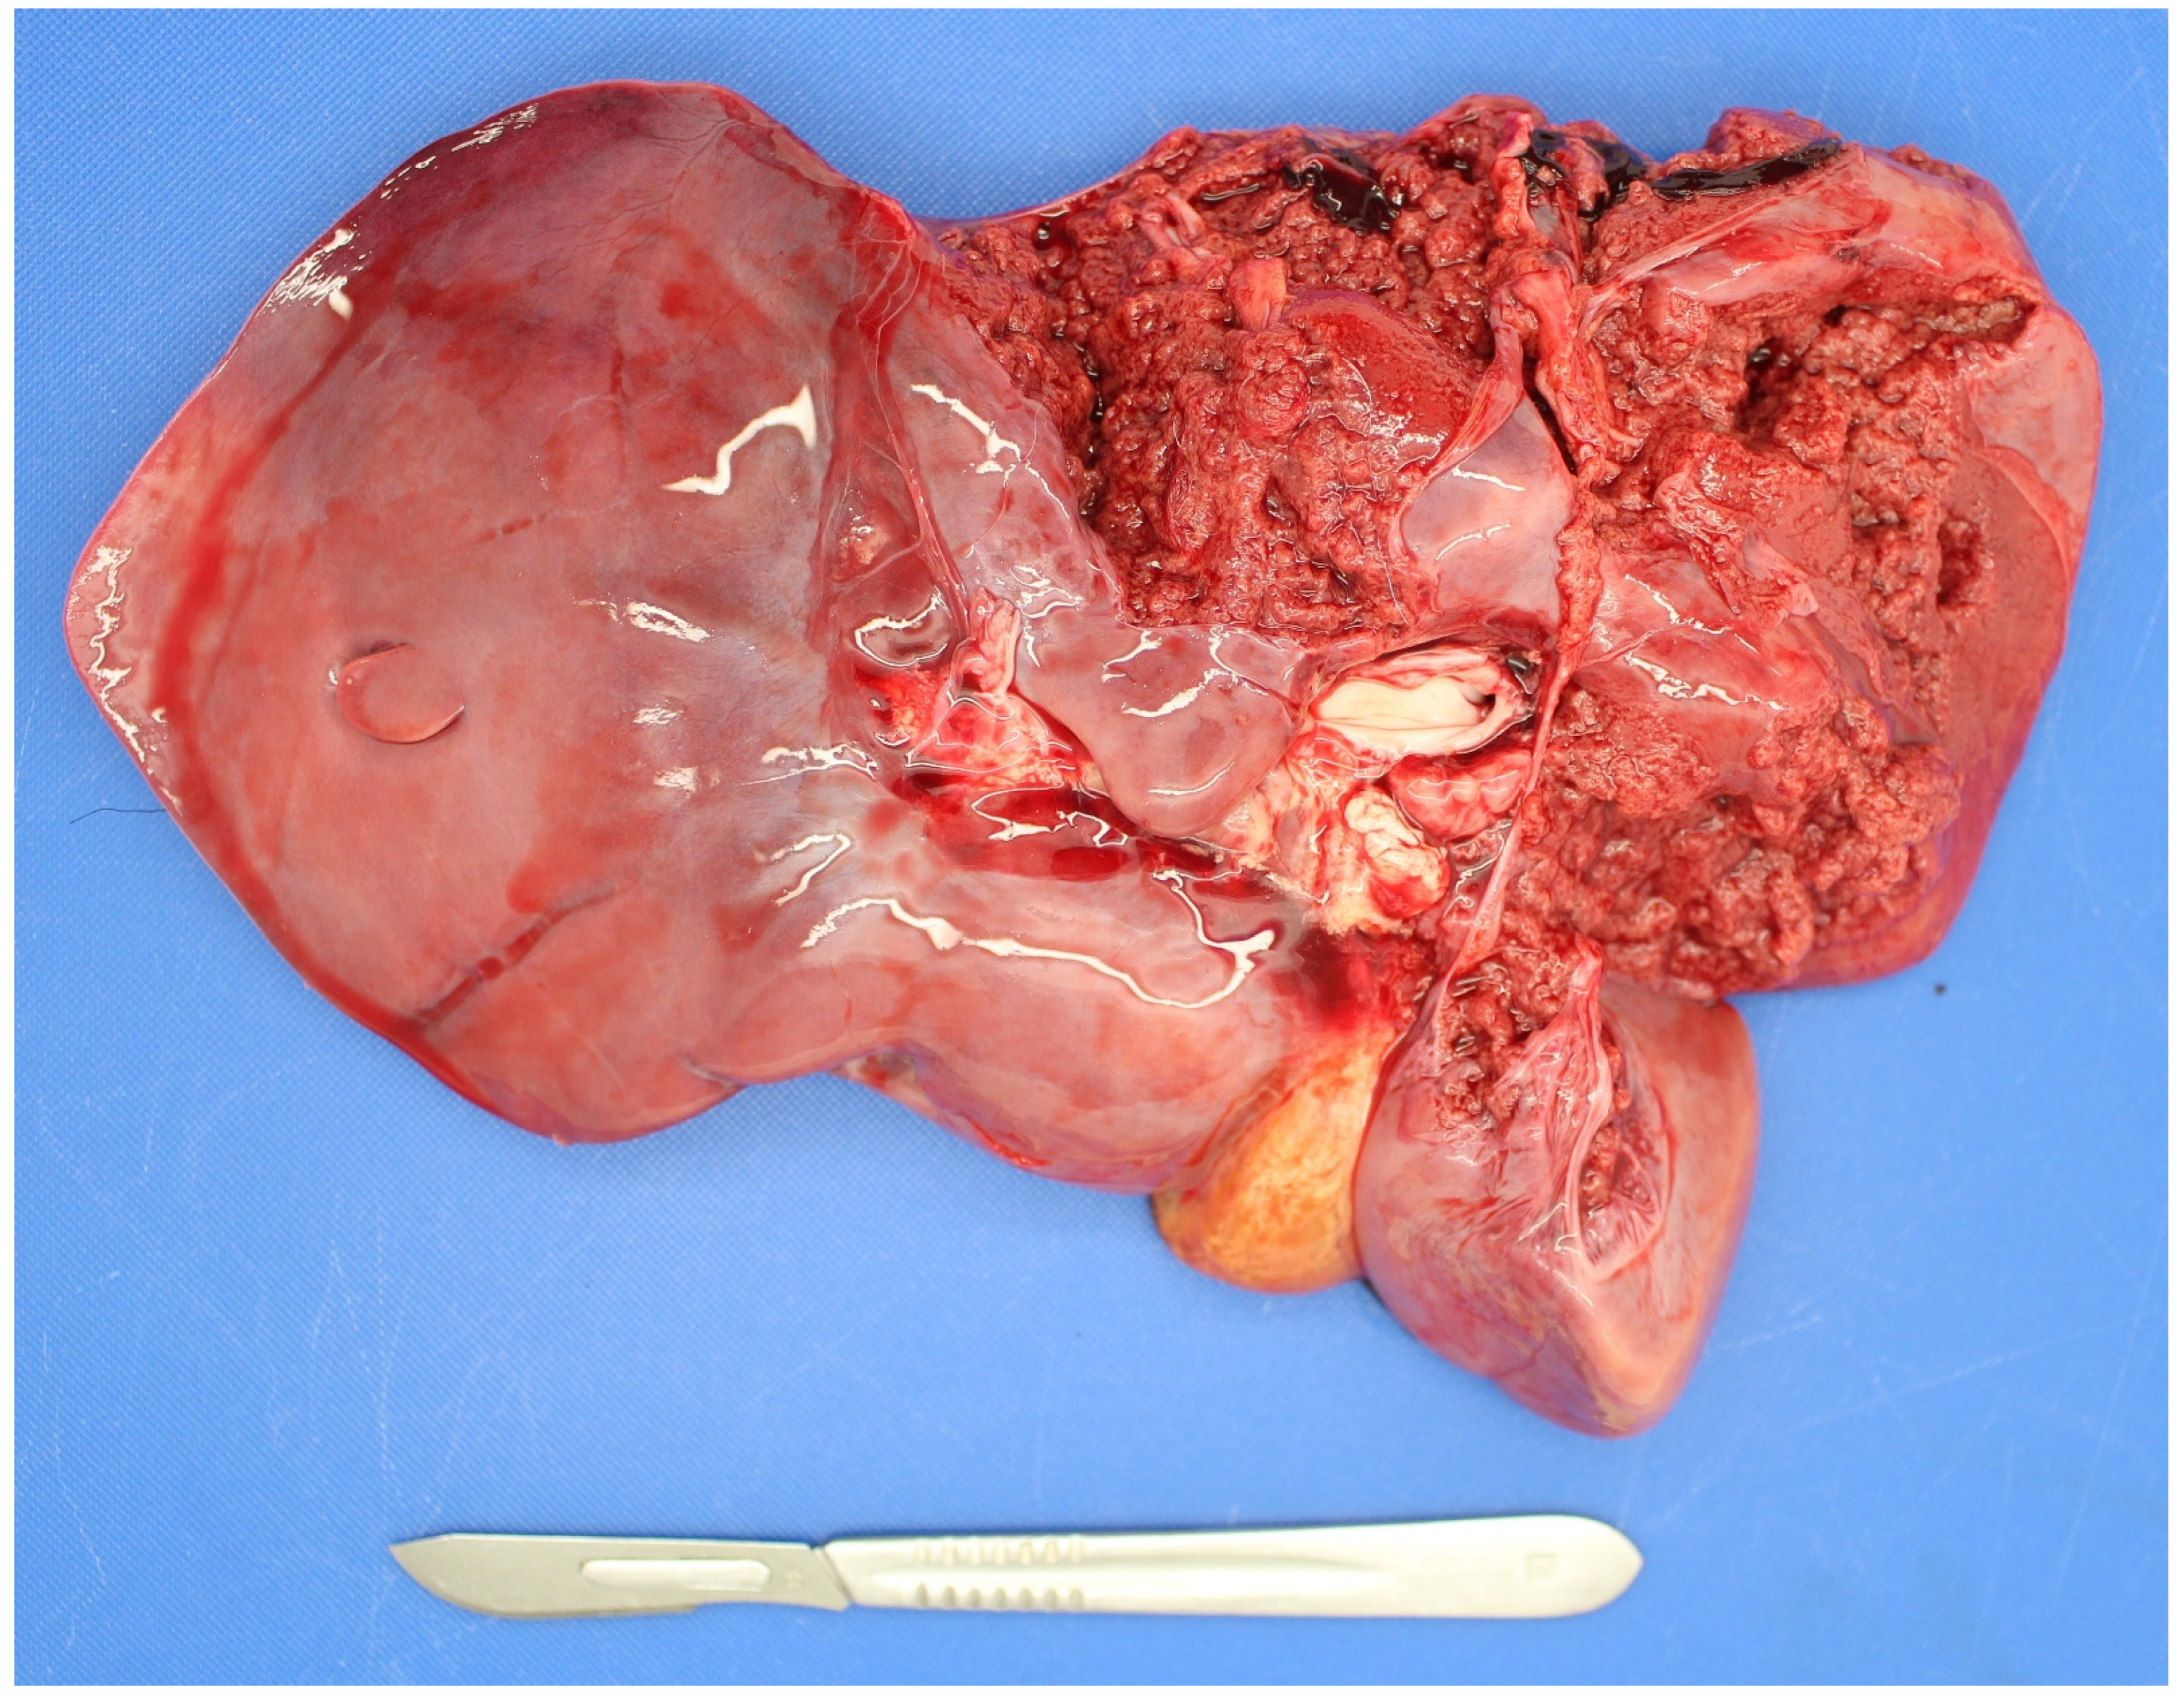

3.5. Examination of the Placenta